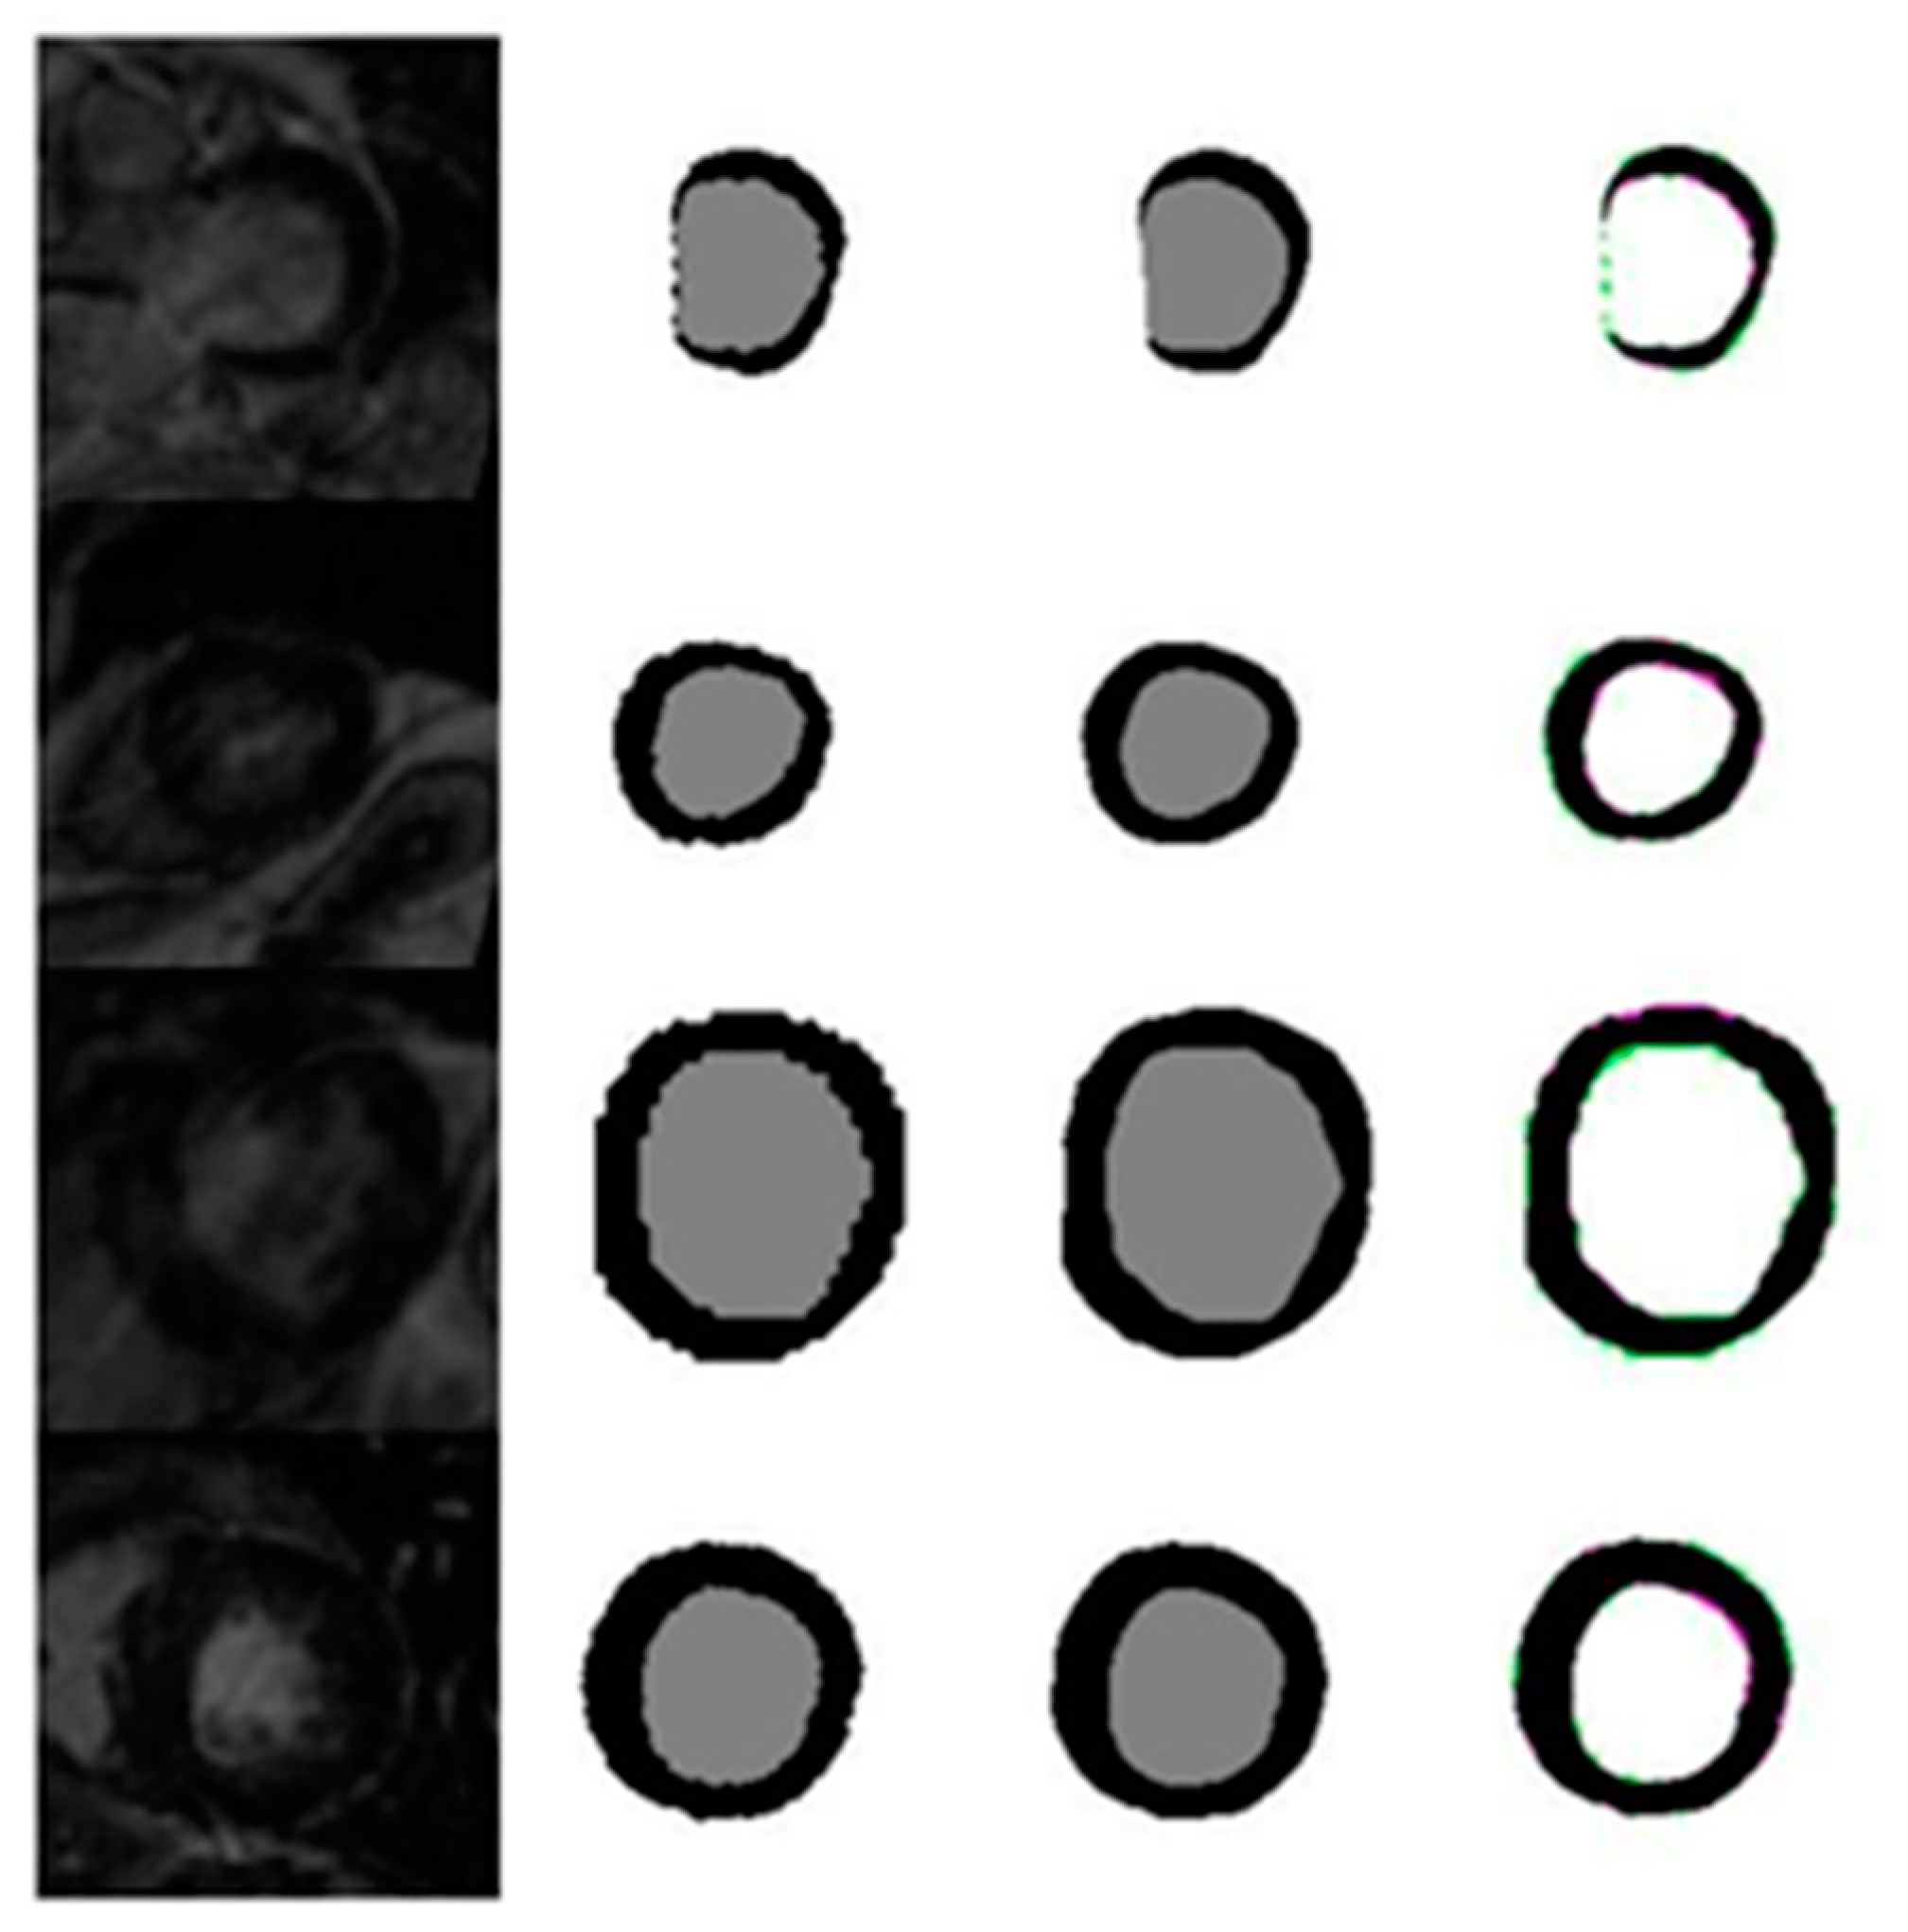

4.1. Evaluation of the Effects of Image Size on the Quality of Automatic Segmentation with U-Net against the GT Segmentation

4.1.6. Evaluation of Automated Segmentation with U-Net and GT Segmentation Using LGE MRI Test Images